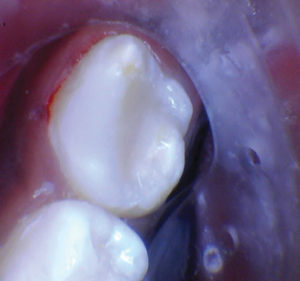

Caso 5

Una adolescente de 13 años presentada para un nuevo examen de paciente. Se observó una gran lesión cariosa en el primer molar permanente superior izquierdo, que presentaba síntomas de pulpitis reversible. Las opciones de tratamiento se discutieron con la paciente y su madre. Mis objetivos personales para este caso eran evitar la exposición de la pulpa y restaurar la forma y la función.

Figura 1. Presentación

clínica inicial del primer molar permanente superior izquierdo con caries

oclusal. |

Figura 2. Cuando la lesión

estaba sin techar, era evidente que había una lesión amplia y profunda. |